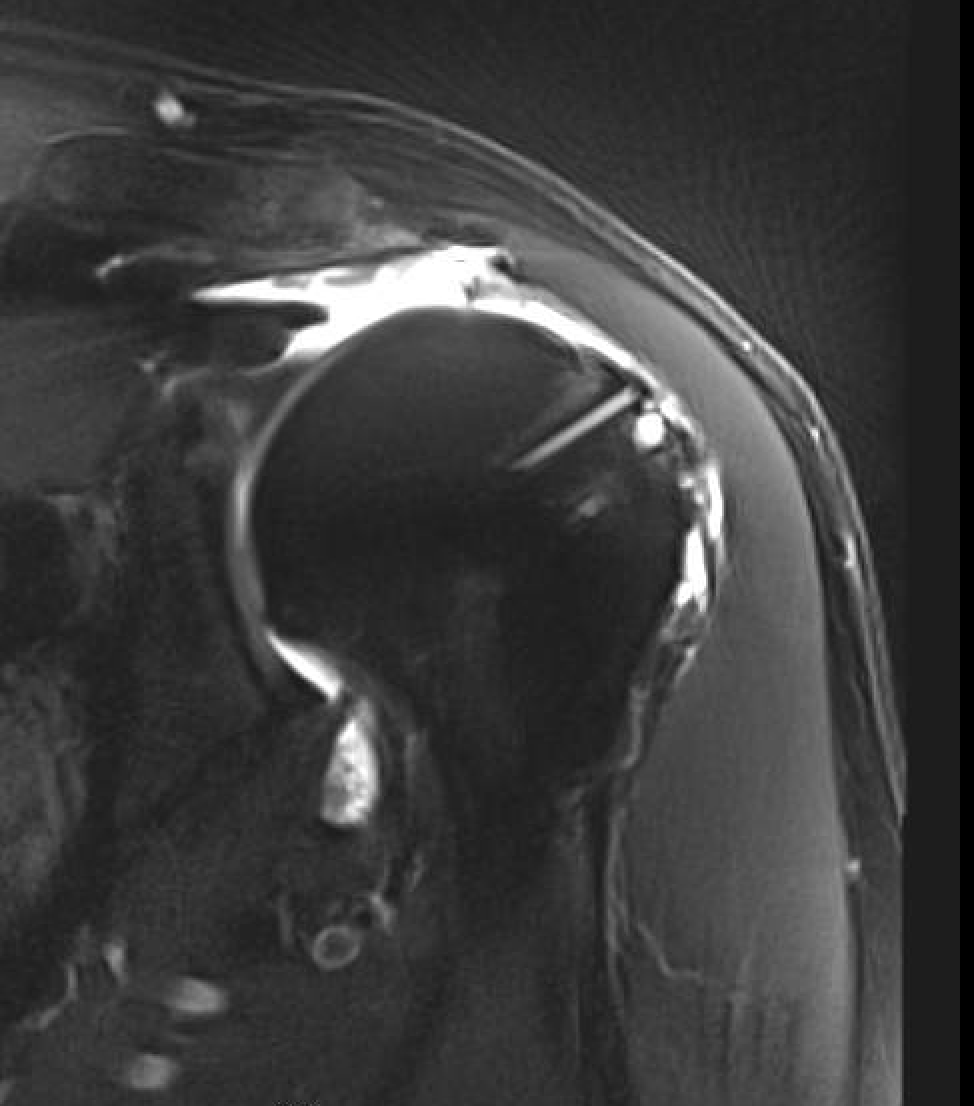

Rotator Cuff Tear Arthropathy Shoulder Arthritis shoulder surgeon Arthritis In Shoulder Rotator Cuff the rotator cuff is a group of muscles and tendons that surround the shoulder joint, keeping the head of the. rotator cuff tear arthropathy is a type of shoulder arthritis that can develop after a massive and prolonged rotator cuff tear. The four rotator cuff tendons in your shoulder wrap around the ball portion of the shoulder joint,. Arthritis In Shoulder Rotator Cuff.